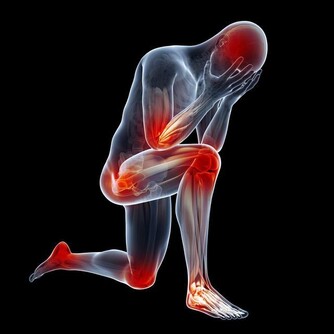

2、免疫力低下

有些人唇皰疹的發病率可能為一年兩次,而有的人可能每個月都會有唇皰疹的症狀。而反復發作的病人是終身攜帶病毒,病毒已經躲到神經結裡面了,當人處於比較疲勞的狀態,抵抗力下降,病毒又會活躍而發病,所以,這類患者則屬於復發性單純皰疹。

當你出現嘴邊長泡,或者口腔潰瘍、感冒、鼻炎等問題,並且都是經常反复,老不好時就要留心免疫力的問題了。